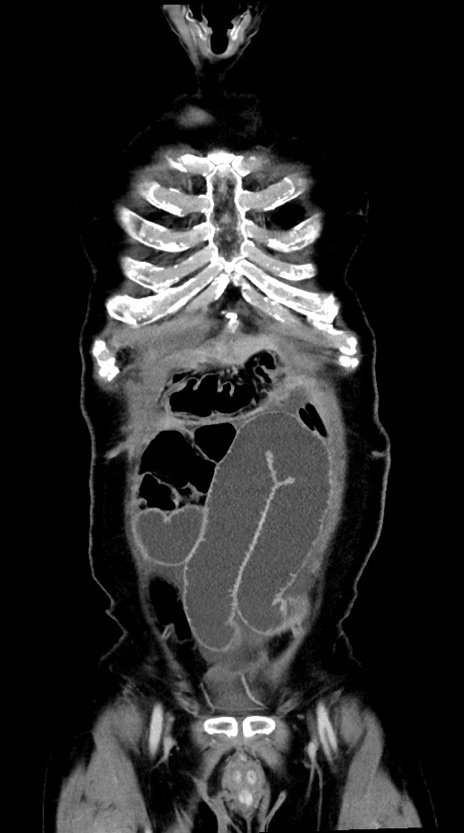

横断像

【症例】60歳代男性

【主訴】嘔吐

【現病歴】胃癌にて胃全摘後。食思不振が悪化し、夜中に嘔吐することがある。

【既往歴】胃癌、胃全摘、脾摘、胆摘後

【データ】WBC 5900、CRP 10.56